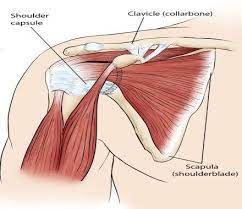

قیمت: 48٬000 تومان - دسته بندی فایل: علوم پزشکیپاورپوینت عضلات کمربند شانه ای

فروش ویژه پاورپوینت حرفه ای عضلات کمربند شانه ای با تخفیف استثنایی فقط 72400 تومان تعداد اسلاید : 34 اسلاید